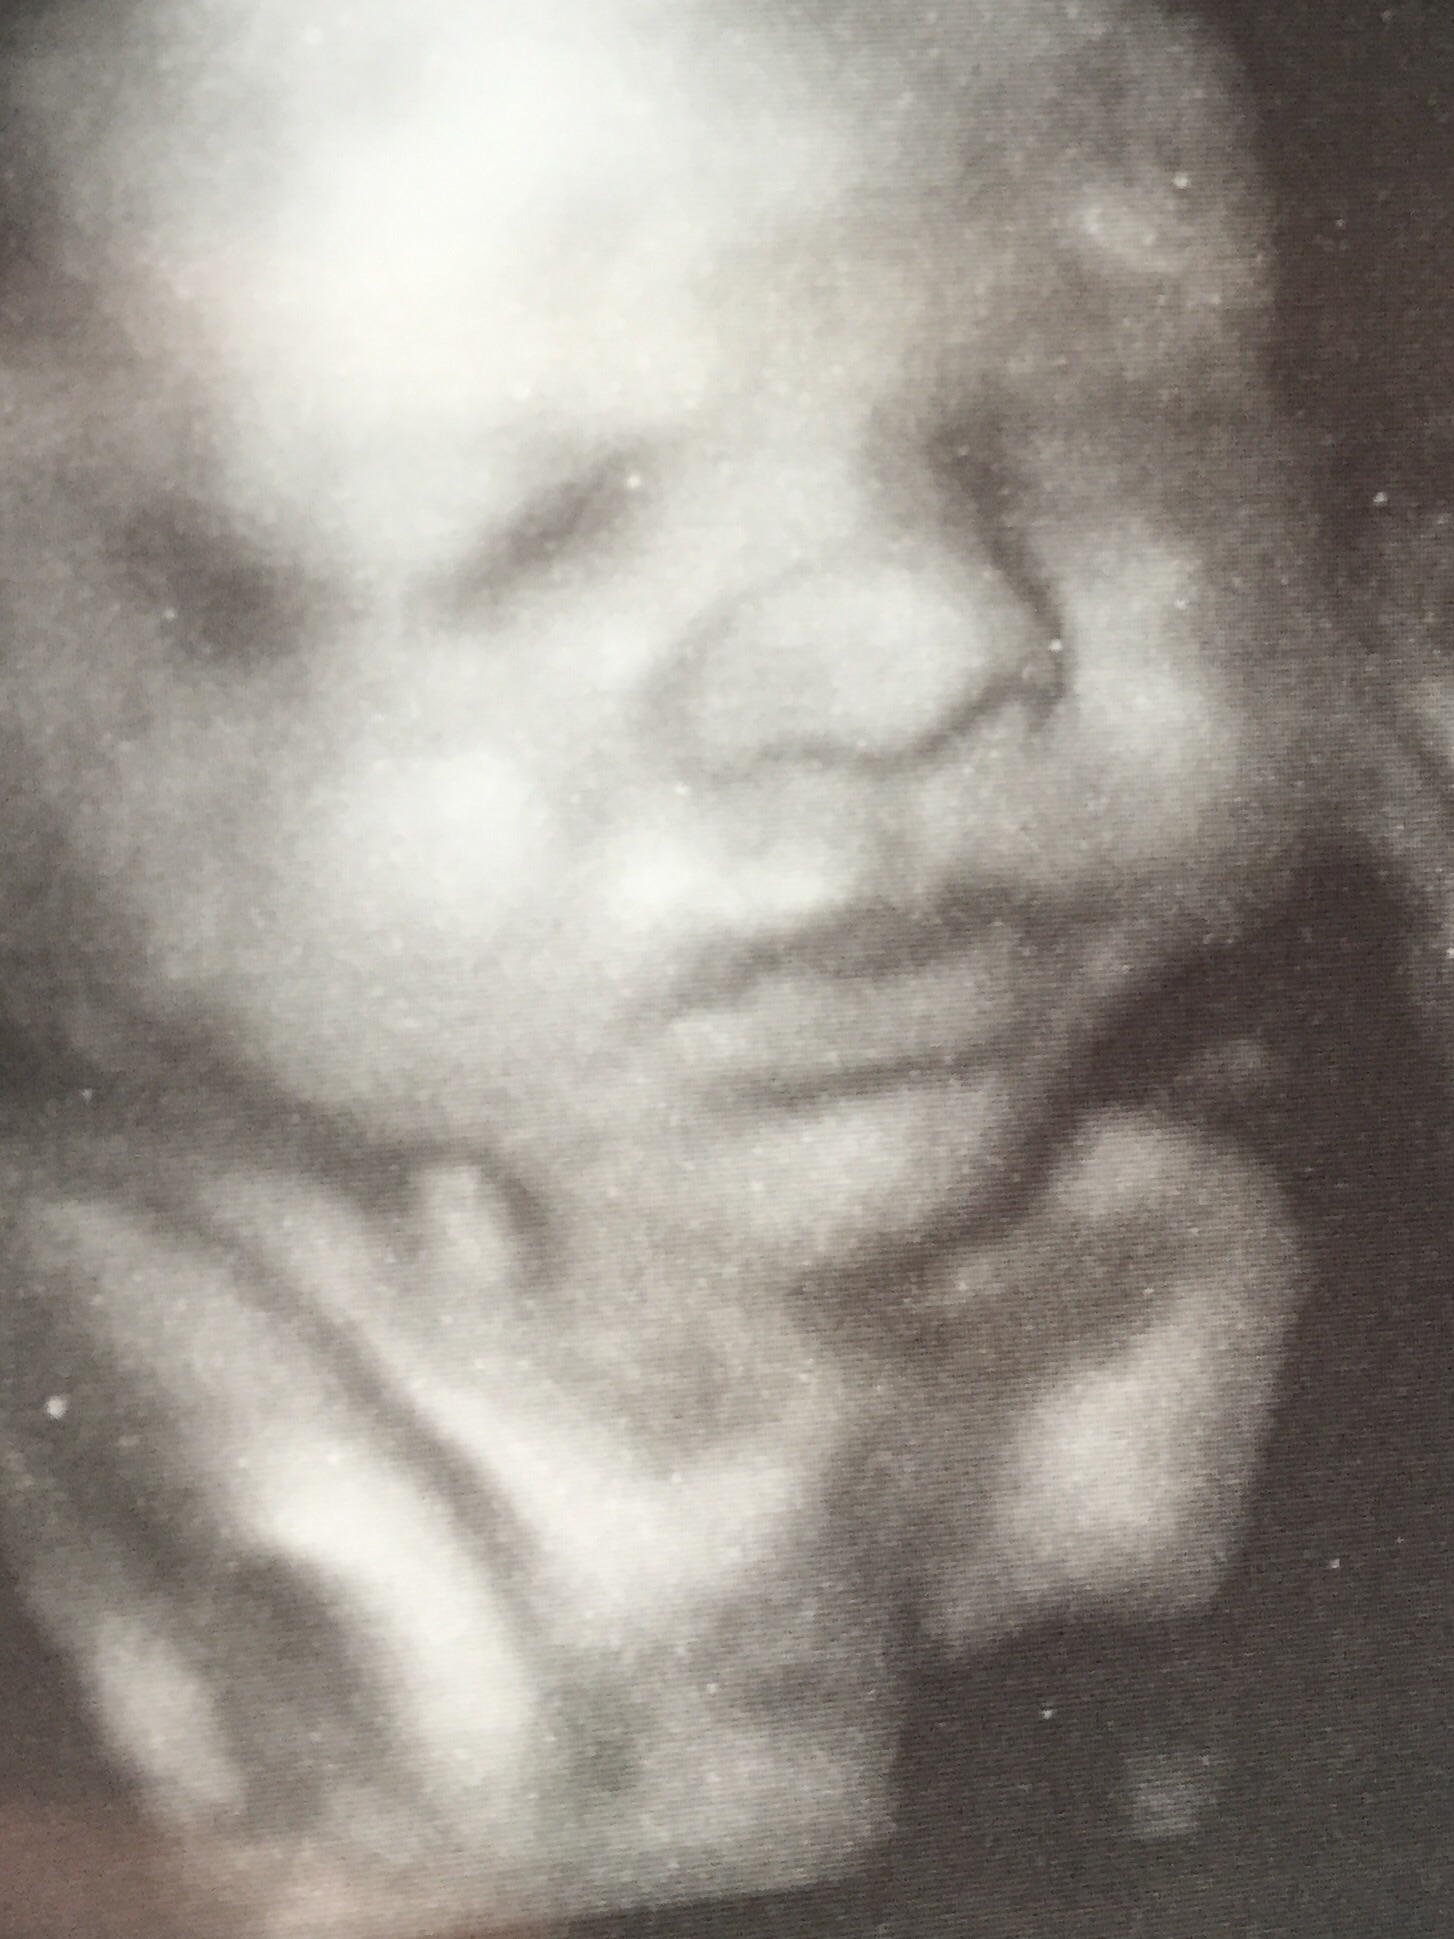

So I just got back from the ultrasound and I was so excited about seeing my alien looking baby (super adorable alien looking baby) that I forgot why I went there to begin with and now idkkkkk if she's breech of not. I THINK I remember her finding her head below my belly button and her legs above. But I'm not sure. Pregnancy brain. Ughhhhh.

Got to see my little man up close and personal today..36 weeks, head down, and measuring 6lbs 14oz (yikes) he kept smiling and sucking in his wrist.. He's so cute :x